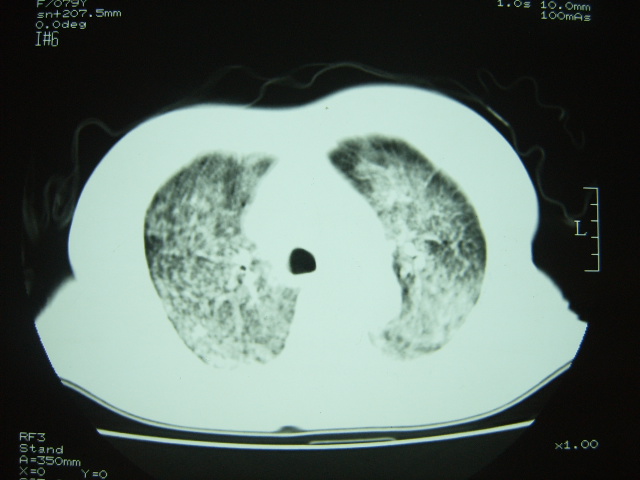

女 79岁,今日高烧,无咳嗽及痰,是否粟粒结核还是?

双肺弥漫小结节状高密度,部分融合,边界不清(因为不是hrct,可能为部分容积效应引起),肺门纵隔内未见肿大淋巴结影。无胸腔积液。

考虑:急性血型播散型肺结核,不除外过敏性肺炎;建议治疗后复查。

双肺弥漫性结节影,双肺上叶为著.纵隔内可见一肿大淋巴结影,密度较高.支持急性血行播散型肺结核.双侧少量胸腔积液.

双肺弥漫基本均匀分布的小结节状高密度影,部分融合。支持急性血性播散性肺结核。

双肺弥漫性粟粒结节影,双肺上叶为著.密度较高. 两侧少量胸水,心影未见明显增大。临床高热病史,考虑炎症性病变。急性播散性肺结核可能大。肺肾综合征?请结合临床进一步检查。

两肺弥漫分布小结节状高密度影,其大小,密度一致,分布均匀,并可见与后胸壁平行的弧状影

诊断:两肺急性血型播散形肺结核

过敏性肺炎不是太像,其主要分布在两肺中下野,呈毛玻璃样片状改变,及模糊的小结节影,病灶短期内可有变化